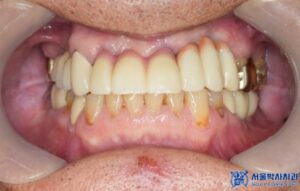

치료 마무리 후 사진입니다.

환자분께서도 최종 보철물을 장착한 후

너무 자연스럽고 불편한 곳도 없다며

매우 만족스러워 하셨습니다.